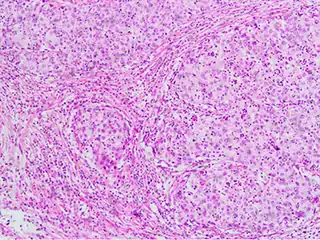

Invasive squamous cell carcinoma of the cervix is characterized by infiltration as irregular anastomosing nests or single cells.[75] This case is poorly differentiated. H&E stain.

Cervical squamous cell carcinoma generally shows diffuse staining of both nuclei and cytoplasm on p16 immuno-

histochemistry (except verrucous variant).[76]